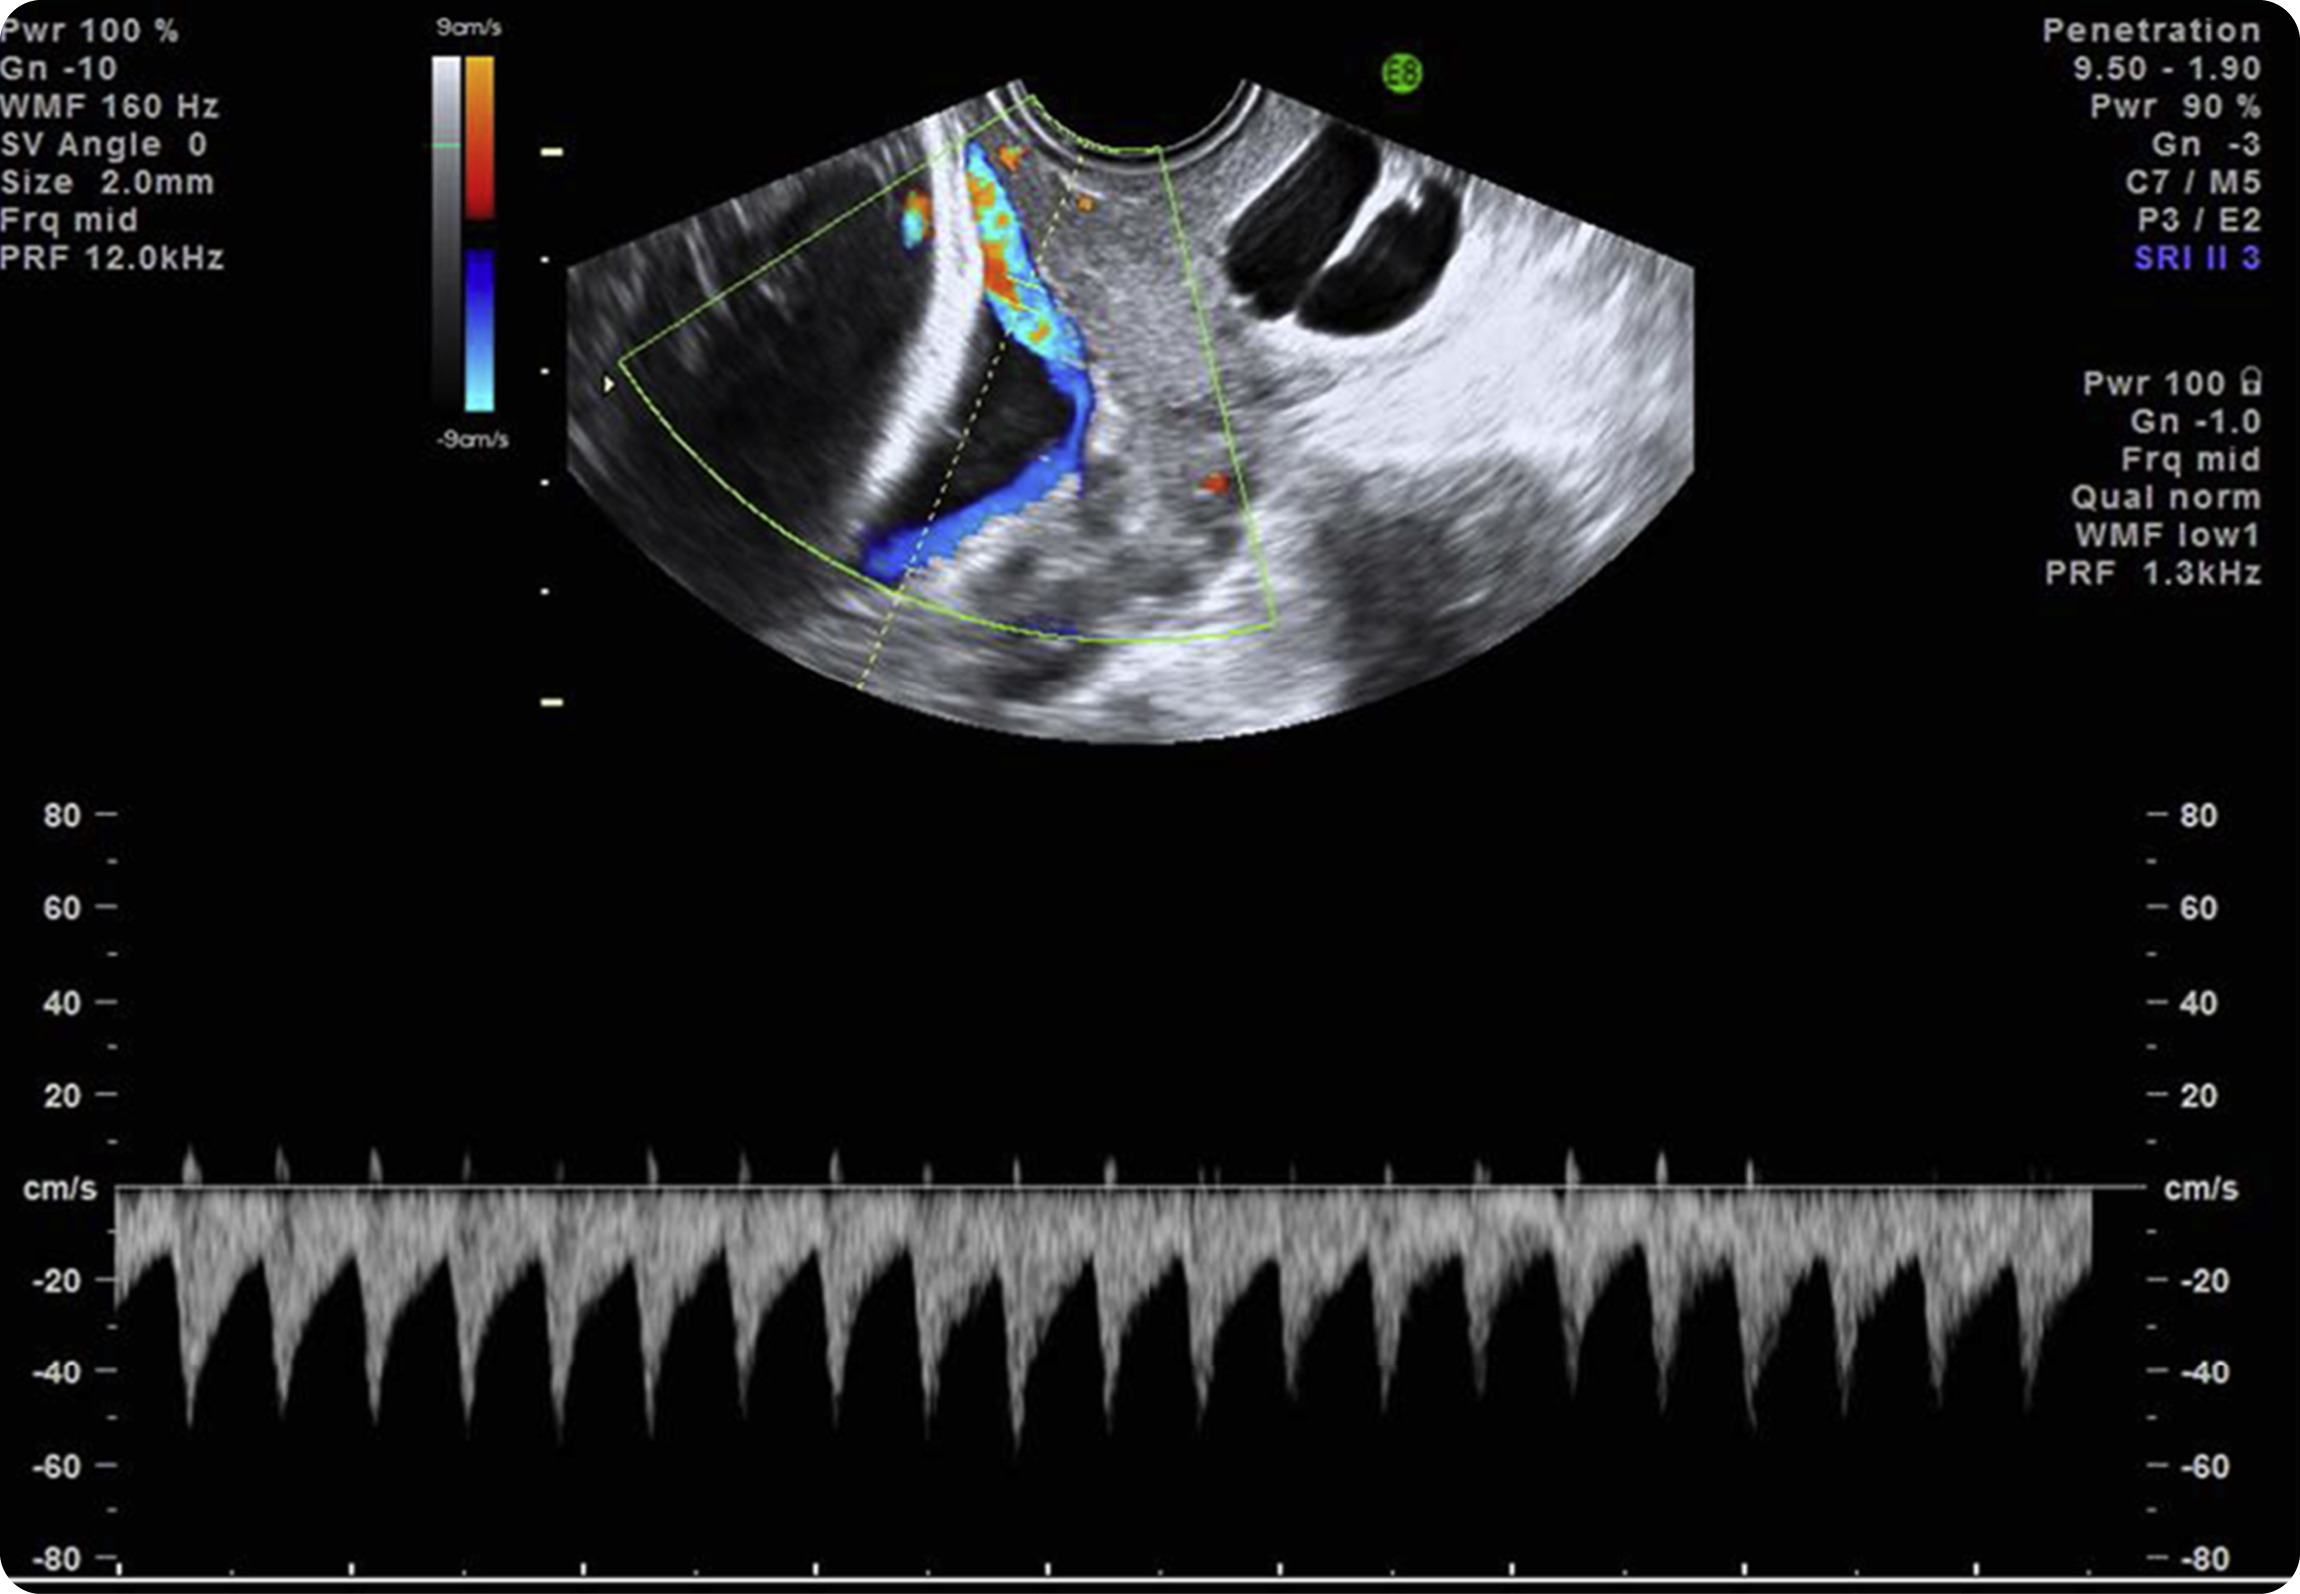

Figure 3. Transvaginal ultrasound scan with color Doppler image and pulsed wave Doppler image shows fetal heart rate

Pulsed wave Doppler of the vessel over the cervical os depicts a fetal heart rate, confirming a diagnosis of vasa previa.

Pulsed wave Doppler of the vessel over the cervical os depicts a fetal heart rate, confirming a diagnosis of vasa previa.

Source: SMFM. Diagnosis and management of vasa previa. Am J Obstet Gynecol 2015.